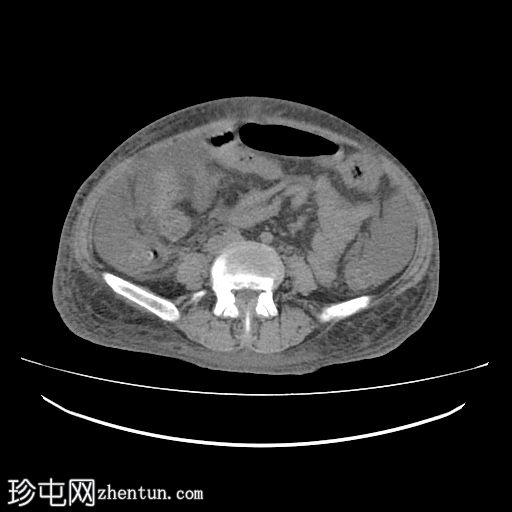

轴位增强扫描

延迟期

肝脏轻度肿大,未见肝内胆管扩张。近端和中段胆总管扩张至8 mm,远端突然中断,门周脂肪间隙增厚。

胰腺轻度肿大,胰周脂肪间隙增厚,符合急性胰腺炎表现。

胃大弯壁内可见一囊肿,大小为7.6 × 4.3 cm,囊壁厚度为2.5 mm,可见强化。脾门处可见另一囊肿,大小为 4.8 × 3.0 cm。

盲肠和升结肠壁水肿增厚,可能为反应性改变。

腹主动脉、脾动脉、腹腔干和肠系膜上动脉可见动脉粥样硬化改变。

中度腹水。双侧轻度胸腔积液(右侧较左侧多)。